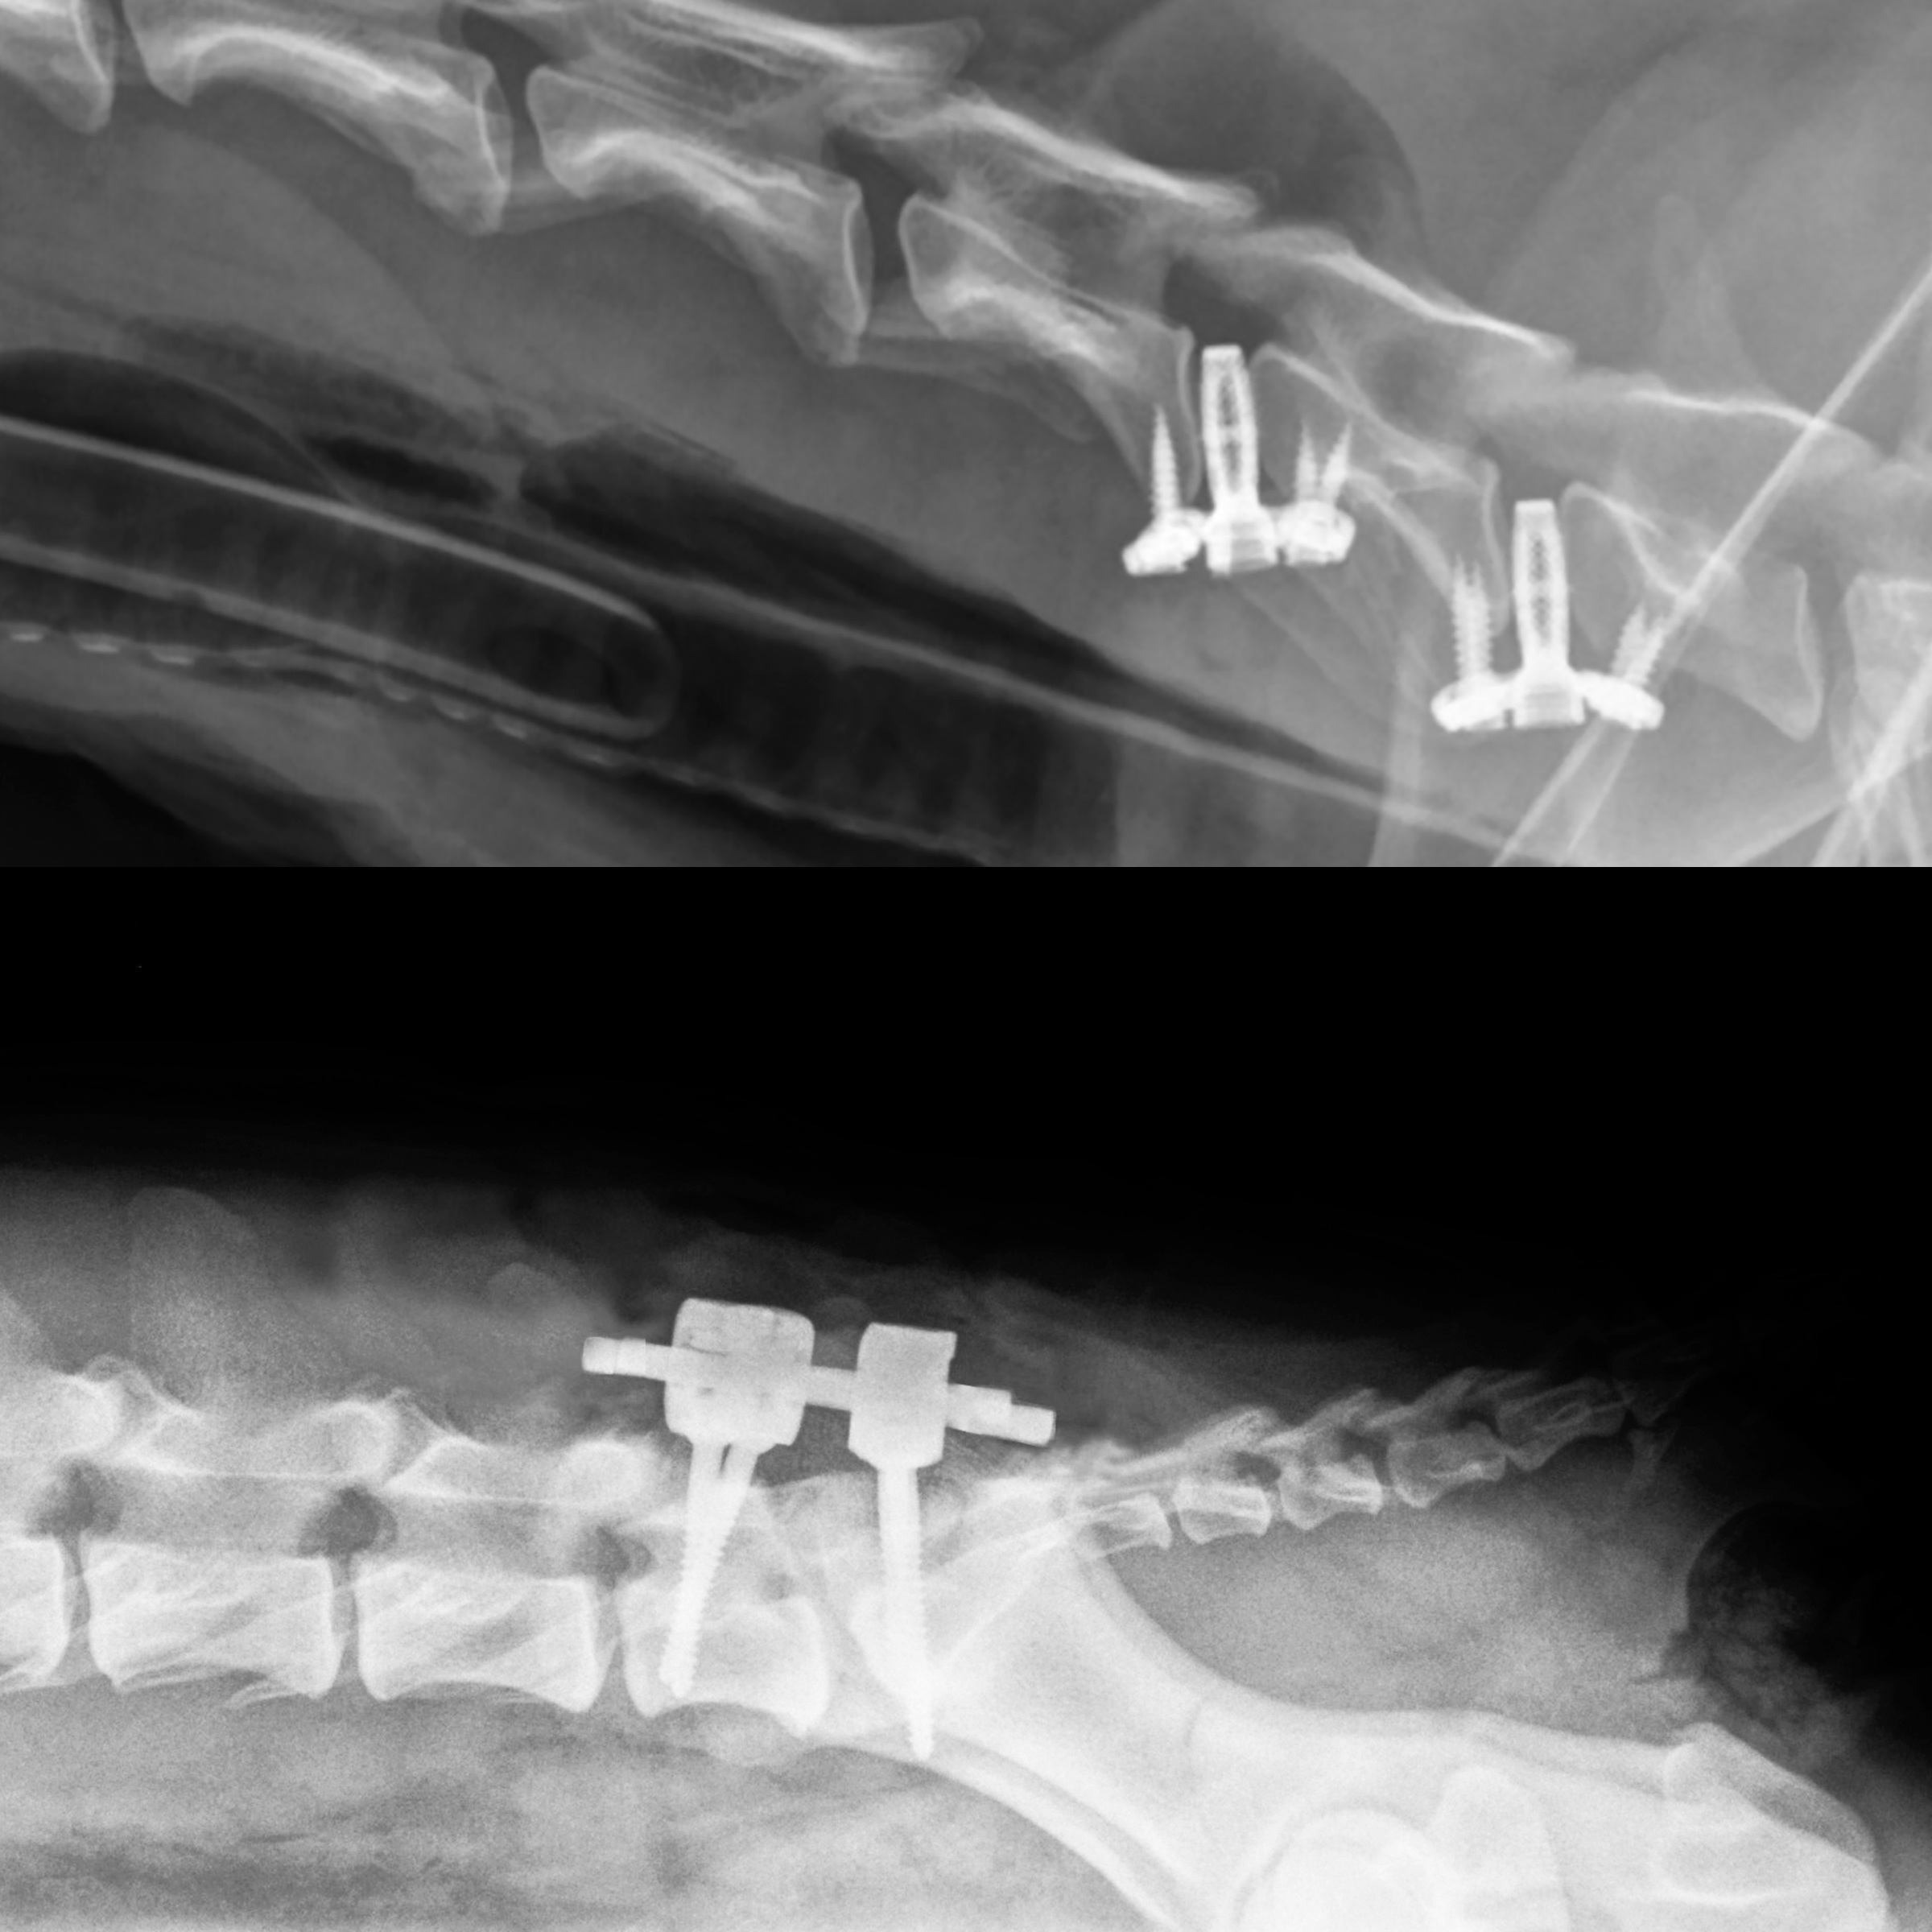

The Spinal Weekend is an intensive 2-day course designed for veterinarians seeking to elevate their expertise in diagnosing and surgically treating complex spinal conditions in dogs—and even cats. Through a carefully curated mix of lectures, interactive sessions, and hands-on labs, this course offers a deep dive into the anatomy, pathology, imaging, and stabilization techniques of the cervical and lumbosacral spine. Day 1: Focus on the Cervical Spine The first day centers around Caudal Cervical Spondylomyelopathy (CCSM)—commonly known as “Wobbler Syndrome.” Participants begin with an in-depth lecture on its pathophysiology and clinical presentation, followed by a session on advanced diagnostic imaging techniques for the cervical spine. A highlight of Day 1 is the detailed walkthrough of the C-LOX implant system, covering surgical planning, instrumentation, and application techniques. The day culminates in a wet lab session using cadaver specimens, providing hands-on experience in C-LOX application under expert guidance. Day 2: Lumbosacral Spine and Stabilization Techniques Day 2 transitions to thoracolumbar and lumbosacral conditions, including both canine and feline cases. The morning covers spinal diseases, imaging interpretation, and surgical indications for stabilization—particularly in Degenerative Lumbosacral Stenosis (DLSS) and spinal fractures. Participants are introduced to advanced spinal implant technologies, including the innovative LeiPED Pedicle Screw System and the LeiCAGE Intervertebral Titanium Cages. The session covers technical details, surgical indications, and dedicated instrumentation for both systems. Together, LeiPED and LeiCAGE are designed to ensure reliable spinal fixation, restore disc height, support fusion, and provide immediate biomechanical stability with long-term osseointegration. In the afternoon, attendees will engage in a combined dry/wet lab, practicing the use of the RL system on spinal models to gain tactile familiarity and technical precision. |

| C-LOX is a spinal disk replacement implant for the cervical spine of dogs. This intervertebral anchored fusion spacer can be used for the treatment of Canine Cervical Spondylomyelopathy (Wobbler Syndrome) and provides a valuable alternative to the more complicated distraction-fusion techniques. C-LOX was developed by RITA LEIBINGER in cooperation with Prof. Dr. Franck Forterre, Bern University (Switzerland). The open sponge Titanium construct of our C-LOX Cages allows for rapid bone growth throughout the cage. |

About LeiPED Pedicle Screw System |

Precision Spinal Stabilization for Canine Patients Developed specifically for the unique anatomical demands of veterinary spinal surgery, the new LeiPED Pedicle Screw & Rod System sets a new standard in vertebral column fixation. With its innovative asymmetric screw head and side-loading rod design, LeiPED offers exceptional stability, optimal anatomical adaptation, and space-saving advantages—making it the superior choice for both routine and complex procedures. |

About LeiCAGE Intervertebral Cages |

Designed to restore intervertebral disc height, support spinal fusion, and ensure immediate biomechanical stability and osseointegration. |